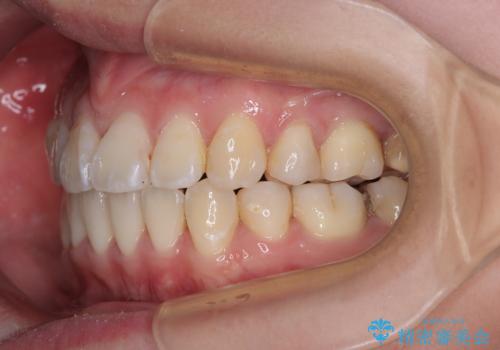

- 上下の出っ歯を気にして来院された患者様です。

口元を積極的に引っ込めるために、上下左右の第一小臼歯を4本抜歯することとしました。

また、上下前歯は舌の突出癖による開咬となっていたため、舌のトレーニングを徹底するよう指示しました。

舌突出癖の改善トレーニングは、仕上がり、治療期間、そして治療後の後戻りに大きな影響を及ぼします。

トレーニングをしっかりと行っていただいたため、スッキリとした口元に仕上がりました。